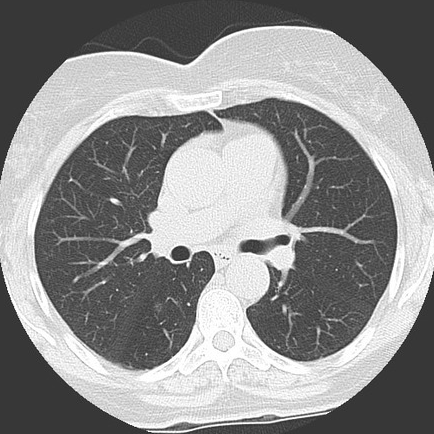

결절을 보기 위해서는 폐실질을 보게 되는데, 결절은 CT 검사 상 하얗게 보입니다. 간유리음영이라고 하는 것은 정상적인 폐 구조물의 음영이 비쳐 보일 정도로 약간만 음영이 증가한 결절을 말합니다. 단단하지 않은 성분으로 이루어져 있기 때문입니다. 정상조직의 음영이 다 보이지 않을 정도로 음영이 증가한 결절은 고형결절이라고 부릅니다.

간유리음영으로 보이는 폐결절은 반드시 추적검사를 해야 합니다. 그 자체로 양성인지 악성인지 알 수 없기 때문입니다. 몇 개월 간격으로 검사를 해서 크기의 변화나 음영의 정도에 차이가 있는지를 확인하게 됩니다. 결절은 최대 2년까지 추적검사를 해서 결론을 내리는데, 아주 드물게는 2년 이상 초과한 시기에 암으로 진단되기도 합니다. 따라서 간유리음영 진단을 받았다면 추적검사를 지속적으로 받는 게 최선입니다.

결절의 형태가 간유리음영성 결절인 경우에는 고형결절에 비해 악성의 빈도가 높습니다. 따라서 3개월 후에 바로 추적 검사를 하는 것이 좋습니다.